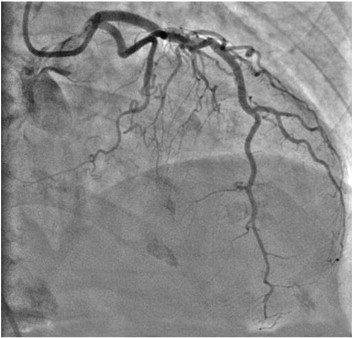

- Angiography.